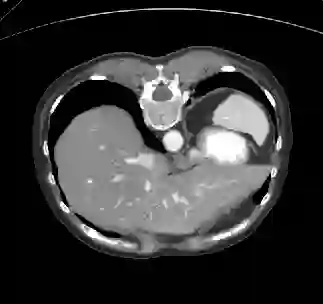

Recently, deep learning methods have achieved state-of-the-art performance in many medical image segmentation tasks. Many of these are based on convolutional neural networks (CNNs). For such methods, the encoder is the key part for global and local information extraction from input images; the extracted features are then passed to the decoder for predicting the segmentations. In contrast, several recent works show a superior performance with the use of transformers, which can better model long-range spatial dependencies and capture low-level details. However, transformer as sole encoder underperforms for some tasks where it cannot efficiently replace the convolution based encoder. In this paper, we propose a model with double encoders for 3D biomedical image segmentation. Our model is a U-shaped CNN augmented with an independent transformer encoder. We fuse the information from the convolutional encoder and the transformer, and pass it to the decoder to obtain the results. We evaluate our methods on three public datasets from three different challenges: BTCV, MoDA and Decathlon. Compared to the state-of-the-art models with and without transformers on each task, our proposed method obtains higher Dice scores across the board.